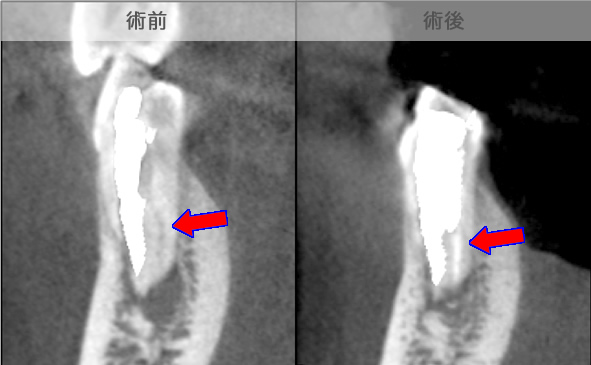

頬側骨壁の根尖部まで無くなっています。

MTA根充後11ヶ月で透過像が消失し、根尖部が正常化しました。

頬側骨の喪失が見られましたが17ヶ月で回復しました。

頬側骨の回復が確認できます。

| 治療説明 | 左下第一小臼歯の頬側根尖部からの排膿、痛みはないそうです。X線画像では根尖部に透過像を認められます。 頬側の骨も失われており、歯髄が死んだことが原因と考えられます。修復物を除去後根管治療を行い、根管充填後、透過像は消失、頬側骨も再生されていました。 |

|---|---|